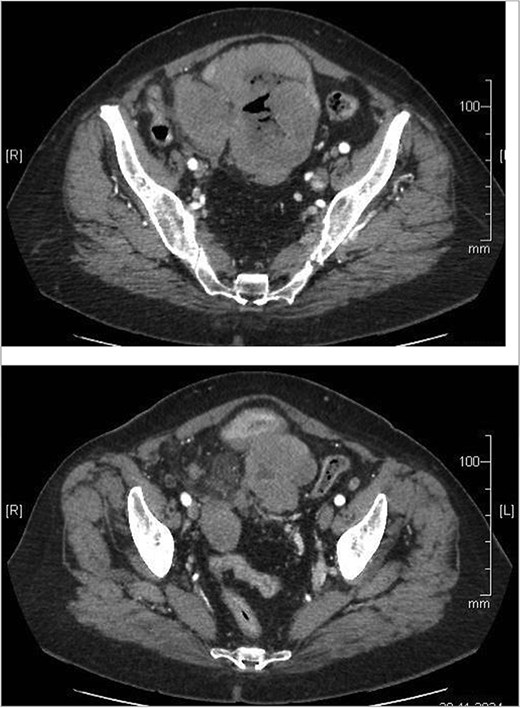

A 74-year-old woman complains of severe constipation, difficult to respond to laxatives and abdominal pain, nausea. A primary abdominal ultrasound (US) examination revealed a hypoechoic tumor formation in the lower abdomen, with uneven outlines and hyperechoic zones in it, with dimensions of ~10 cm/day (Fig. 1). The patient was referred for a computed tomography (CT) scan of the abdomen, which revealed a soft tissue formation with axial dimensions of 130/93 mm heterogeneous structure and infiltrative growth, affecting a segment of the ileum and an adjacent dilated small intestinal loop (Fig. 2). Secondary dissemination along the peritoneum with many soft tissue formations of different sizes formed in the abdomen and small pelvis. Identical lesions are described in the structures of both ovaries bilaterally, the larger of which is 47/34 mm/day. Laboratory parameters revealed anemia with values of Hg-103 g/L, and low values of total protein-60 g/L. The patient has a history of Hashimoto’s thyroiditis and is on replacement therapy with L-thyroxine. During hospitalization, she showed good compensation with a slightly increased TSH- 4.88 mU/L (normal 0.27–4.2) and normal FT4–17.7 pmol/L (normal 12–22). Tumor markers CEA, CA 125, and CA 19-9 were not elevated.

Abdominal CT showing small bowel tumor and similar to both ovaries.